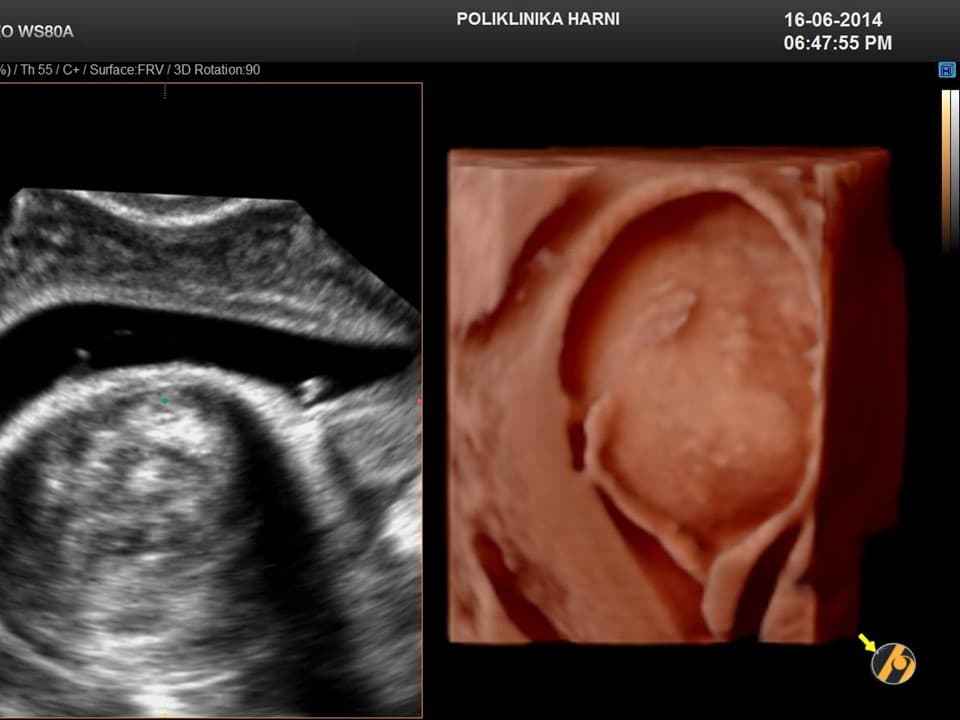

Dijagnoza

Dijagnoza mioma postavlja se temeljem anamnestičkih podataka, ginekološkog i ultrazvučnog pregleda. Ponekada su, osobito kod gigantskih mioma nužne dopunske metode kao što su intravenska urografija, CT ili MRI zdjelice, kako bi se u planiranju operativnog zahvata mogao procijeniti utjecaj mioma na okolne organe, a time i rizik povrede tih organa tijekom operacije.

Dijagnoza se postavlja ginekološkim pregledom i slikovnim pretragama.